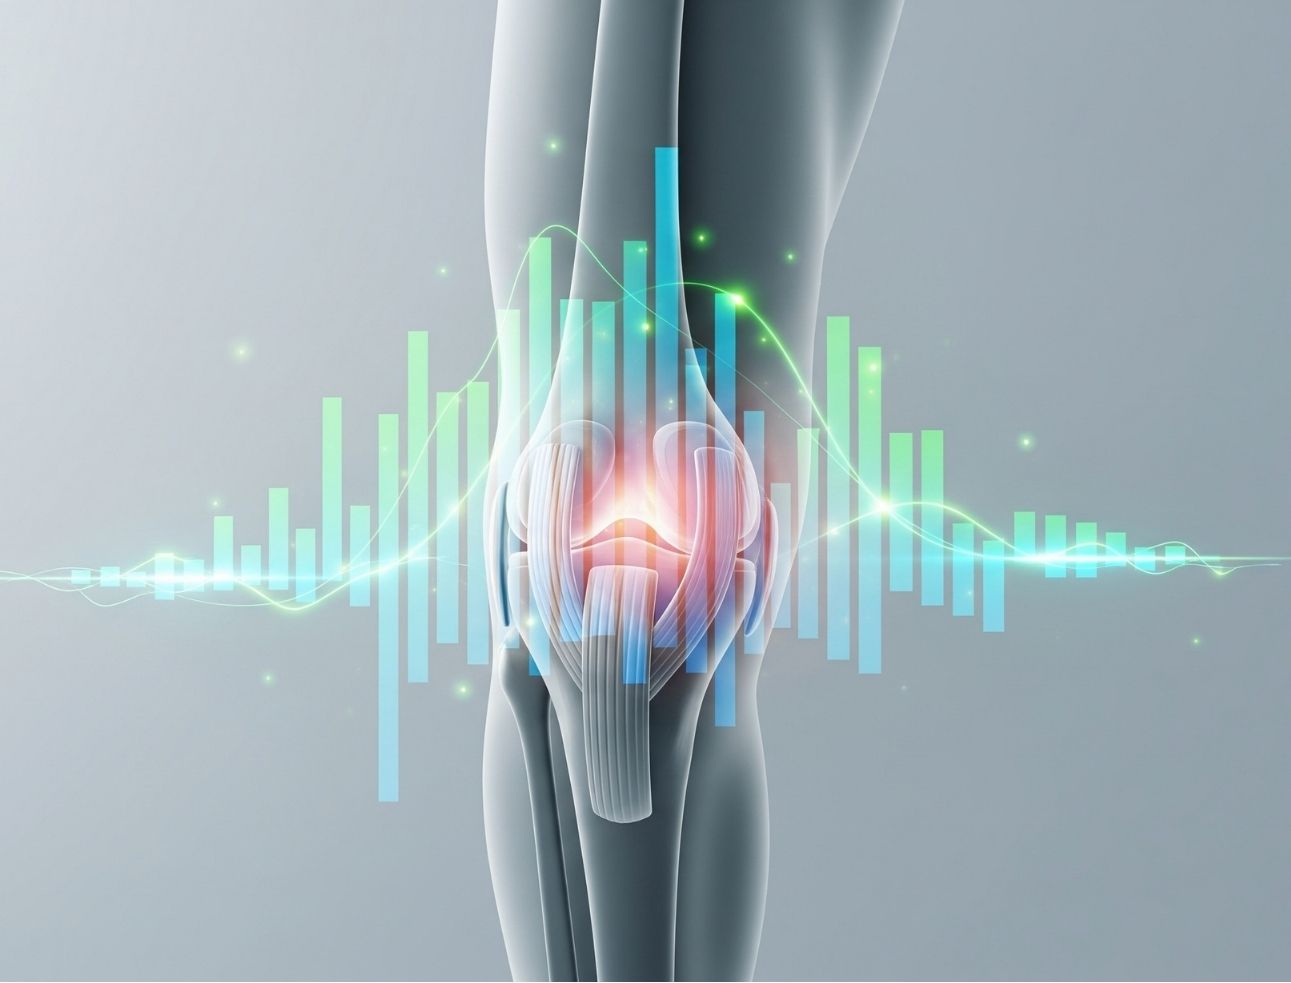

Osteoarthritis is a degenerative joint condition that affects millions worldwide, leading to joint pain, inflammation, and reduced mobility. It commonly impacts the knees, hips, spine, hands, and feet, and is characterized by the breakdown of cartilage, inflammation of the synovial membrane, and weakening of ligaments and muscles. Ostizeel™ has been developed as an innovative response to these challenges.

Ostizeel™ is a synergistic formulation of Palmitoylethanolamide (PEA) and Cucumis sativus extract, designed to act on both nociceptive and neuropathic pain pathways. These two mechanisms are central to the development and persistence of osteoarthritis pain. Nociceptive pain arises from joint tissue damage and inflammation, while neuropathic pain results from nerve sensitization and neuroinflammation. By addressing both, Ostizeel™ delivers targeted and lasting relief.

Ostizeel™ has been scientifically formulated to modulate critical molecular mechanisms that contribute to osteoarthritis progression. It targets mast cells, TRPV1 receptors, PPAR-α, and microglial cells all of which play key roles in pain transmission and inflammation. The result is a dual-action response that reduces both inflammatory and neuropathic pain.